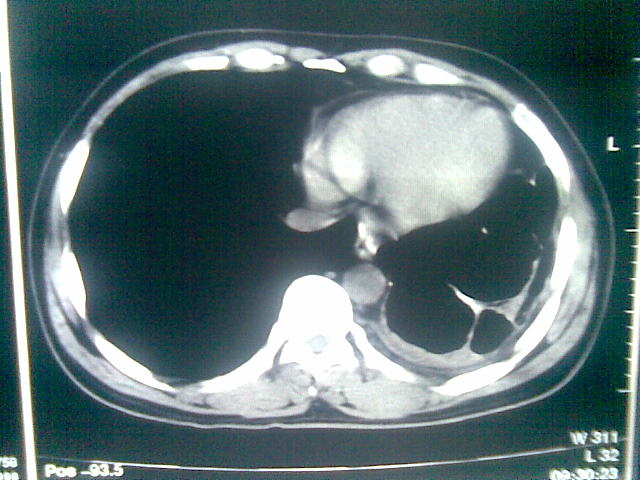

标题: CT23981:男,38岁阑尾炎术后透视胸腔积夜!做CT如下!积液包 [打印本页]

标题: CT23981:男,38岁阑尾炎术后透视胸腔积夜!做CT如下!积液包

可能与阑尾术后关系不太大,1.胸膜增厚粘连见少量气体。包裹脓气胸?左侧网膜囊脓肿?

.胸膜增厚粘连见少量气体。包裹脓气胸

左侧胸膜增厚、粘连+包裹液气胸。